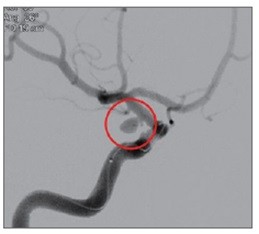

![]() |

| ▲ |

뇌동맥류로 인해 부풀어 오른 혈관이 터지면 뇌출혈이 생긴다. 이 경우 사망 위험이 크게 증가하고 뇌에 영구적 손상이 가해져 언어장애, 운동장애 등이 유발된다.

뇌동맥류 파열은 혈압으로 인한 뇌압 상승이 주 원인이다. 따라서 혈압에 영향을 미치는 고혈압, 당뇨병, 고지혈증 등의 질환이 위험인자가 될 수 있다. 혈압을 높이는 음주, 비만, 흡연 등의 생활습관도 마찬가지다. 또한 갑자기 무거운 물건을 들거나 힘을 줘서 대변을 보는 등 혈압을 높이는 행동도 뇌동맥류 파열 위험을 높인다. 같은 이유로 격렬한 운동, 기침 등도 위험인자가 될 수 있다.